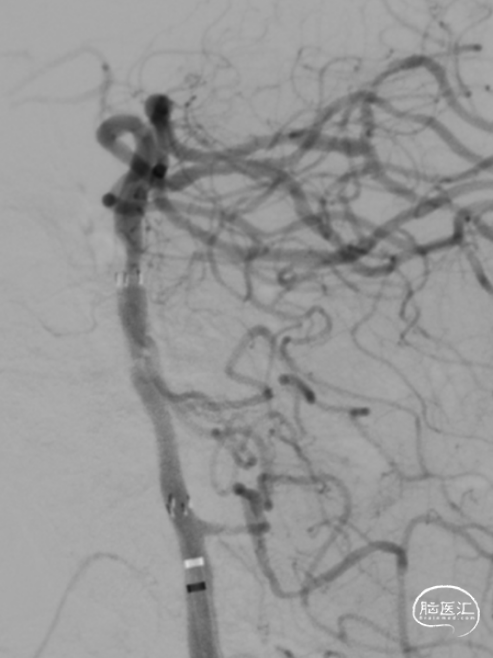

急诊DSA:Ⅱ型弓,基底动脉AICA以远未见显影。

第二次拉栓后造影,血管再通,支架内再狭窄处理风险极高,且目前前向血流3级,对比造影时影像支架未有移位。

基底动脉支架内再狭窄导致的闭塞取栓风险高,操作复杂,Syphonet®取栓支架通体显影,可以清楚看见取栓支架与基底动脉内原有支架的关联,避免支架移位,提高手术安全。